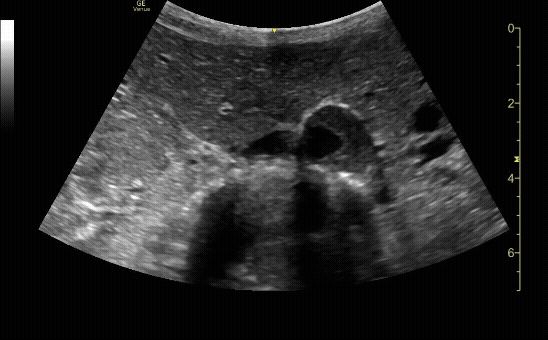

Proximal sagittal (long) view showing the SMA branching off of the aorta.

c/o Michael Dorritie, MD